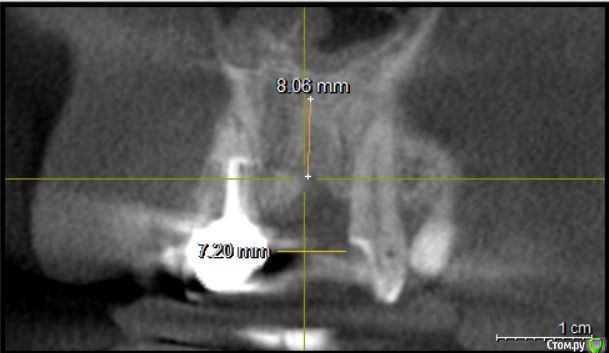

Evikrol Опубликовано 27 мая, 2018 Поделиться Опубликовано 27 мая, 2018 Почему же. Посмотрите на кт как располагается коронка соседнего зуба, я предположил что так, судя по антагонисту. Очень даже на винтовую получается Ссылка на комментарий

Kazankov.Egor Опубликовано 28 мая, 2018 Автор Поделиться Опубликовано 28 мая, 2018 Почему же. Посмотрите на кт как располагается коронка соседнего зуба, я предположил что так, судя по антагонисту. Очень даже на винтовую получается вот это миллиметраж! Спасибо! Идею понял, я бы поставил по кости (линии замера высоты) и конец... Ссылка на комментарий